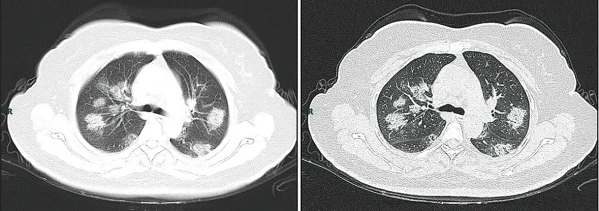

КТ грудной клетки иногда может помочь идентифицировать и охарактеризовать патологию лёгких и дать неспецифические результаты при инфекции COVID-19. Систематический обзор результатов компьютерной томографии грудной клетки у 919 пациентов описал типичное раннее проявление COVID-19 как «двустороннее мультилобарное помутнение матового стекла (GGO) с периферическим или задним распределением»[18]. Одно исследование показало, что чувствительность КТ к инфекции COVID-19 составила 98 % по сравнению с чувствительностью ОТ-ПЦР на 71 %; однако это было сделано в китайской провинции Ухань и не подлежит обобщению[19]. Наиболее распространёнными результатами компьютерной томографии были двустороннее затухание матового стекла (пятнистое или рассеянное) с субплевральным доминированием, сумасшедшей укладкой и консолидацией на более поздних стадиях.[20] Эти данные являются неспецифичными и обнаруживаются также при других типах пневмонии. Небольшое исследование показало, что китайские рентгенологи продемонстрировали чувствительность 72-94 % и 24-94 % в дифференцировании COVID-19 от других типов вирусной пневмонии с использованием компьютерной томографии[21]. Ни одно исследование ещё не подтвердило точность и дискриминационную ценность компьютерных томографий, чтобы отличить COVID-19 от других вирусных пневмоний. Поэтому CDC не рекомендует КТ для первоначального скрининга, как подчёркивалось в звонке COCA в четверг, 5 марта. Люди с подозрением на COVID-19 должны проходить ОТ-ПЦР, которая является наиболее специфическим тестом[22].